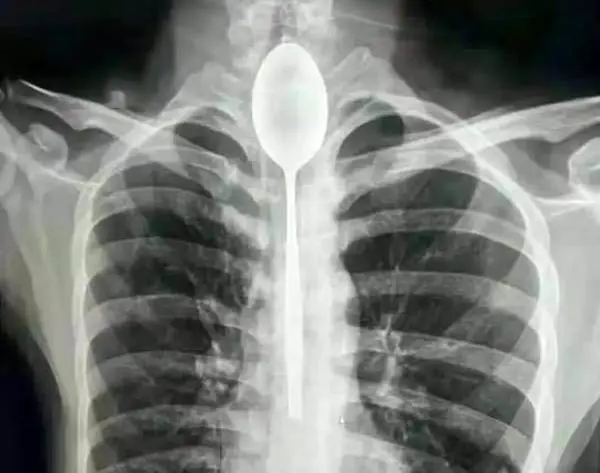

این مرد قاشق 20 سانتی را قورت داد تا شرط را ببرد+عکس

رکنا: خارج کردن قاشق از داخل بدن مرد چینی که به خاطر یک شرط بندی این کار را کرده بود پس از یک سال انجام شد.

مرد چینی در یک شرط بندی احمقانه قاشق 20 سانتی را بلعید و از آنجایی که مشکلی در خوردن و آشامیدن نداشت تا یکسال این قاشق داخل گلوی وی ماند.

مرد چینی قاشق فلزی 8 اینچی را به عنوان یک شیرین کاری احمقانه در سال گذشته بلعید. قاشق در مری او گیر کرد، اما چون به راحتی می توانست بخورد و بنوشد، هرگز به دنبال کمک پزشکی برای بیرون آوردن آن نبود. او می گوید تنها چند روز پیش به علت ضربه وارد شده به قفسه سینه ، دچار درد قفسه سینه شد ؛ این جملات قسمتی از ماجرای عجیبی بود که در این بخش از سرگرمی Hobby نمناک خواهید خواند.قاشق

مردی که نامش فاش نشده است از منطقه جین جیانگ چین به پزشکان گفت :او یک قاشق فولادی ضد زنگ را در طی یک شرط درحالت مستی بلعیده . او به دوستانش گفته که می تواند قاشق را ببلعد و بعد دوباره با ریسمانی که به دسته قاشق می بندد آن را بیرون آورد . در آن زمان برای او حتما فکر خوبی به نظر می رسید، اما همه چیز طبق برنامه پیش نرفت و قاشق در گلوی او گیر کرد. به جای رفتن به بیمارستان، مرد منتظر ماند تا ببیند آیا قاشق به طور عادی از خوردن و نوشیدن جلوگیری می کند یا نه ؛ این طور نبود، پس در مری ماند تا سال گذشته.

قاشق مدت طولانی در سینه او مانده بود و براثر ضربه ای که به سینه او وارد شده بود باعث درد شدید و تنفس بدبو او شده بود . سرانجام به بیمارستان عمومی جین جیانگ رفت و به پزشکان گفت یک سال است که قاشق فلزی در مری او گیر کرده است.

پزشکان در بیمارستان عمومی جین جیانگ پس از بحث در مورد بهترین مسیر عمل تصمیم گرفتند که بهترین راه خارج کردن قاشق ، از طریق دهان بوده است. داروی بی هوشی به بیمار دادند و یک تیم دو ساعت تلاش کردند تا با استفاده از تجهیزات آندوسکوپی ، قاشق 8 اینچی را بیرون آوردند.خواندنی های رکنا را در اینستاگرام دنبال کنید